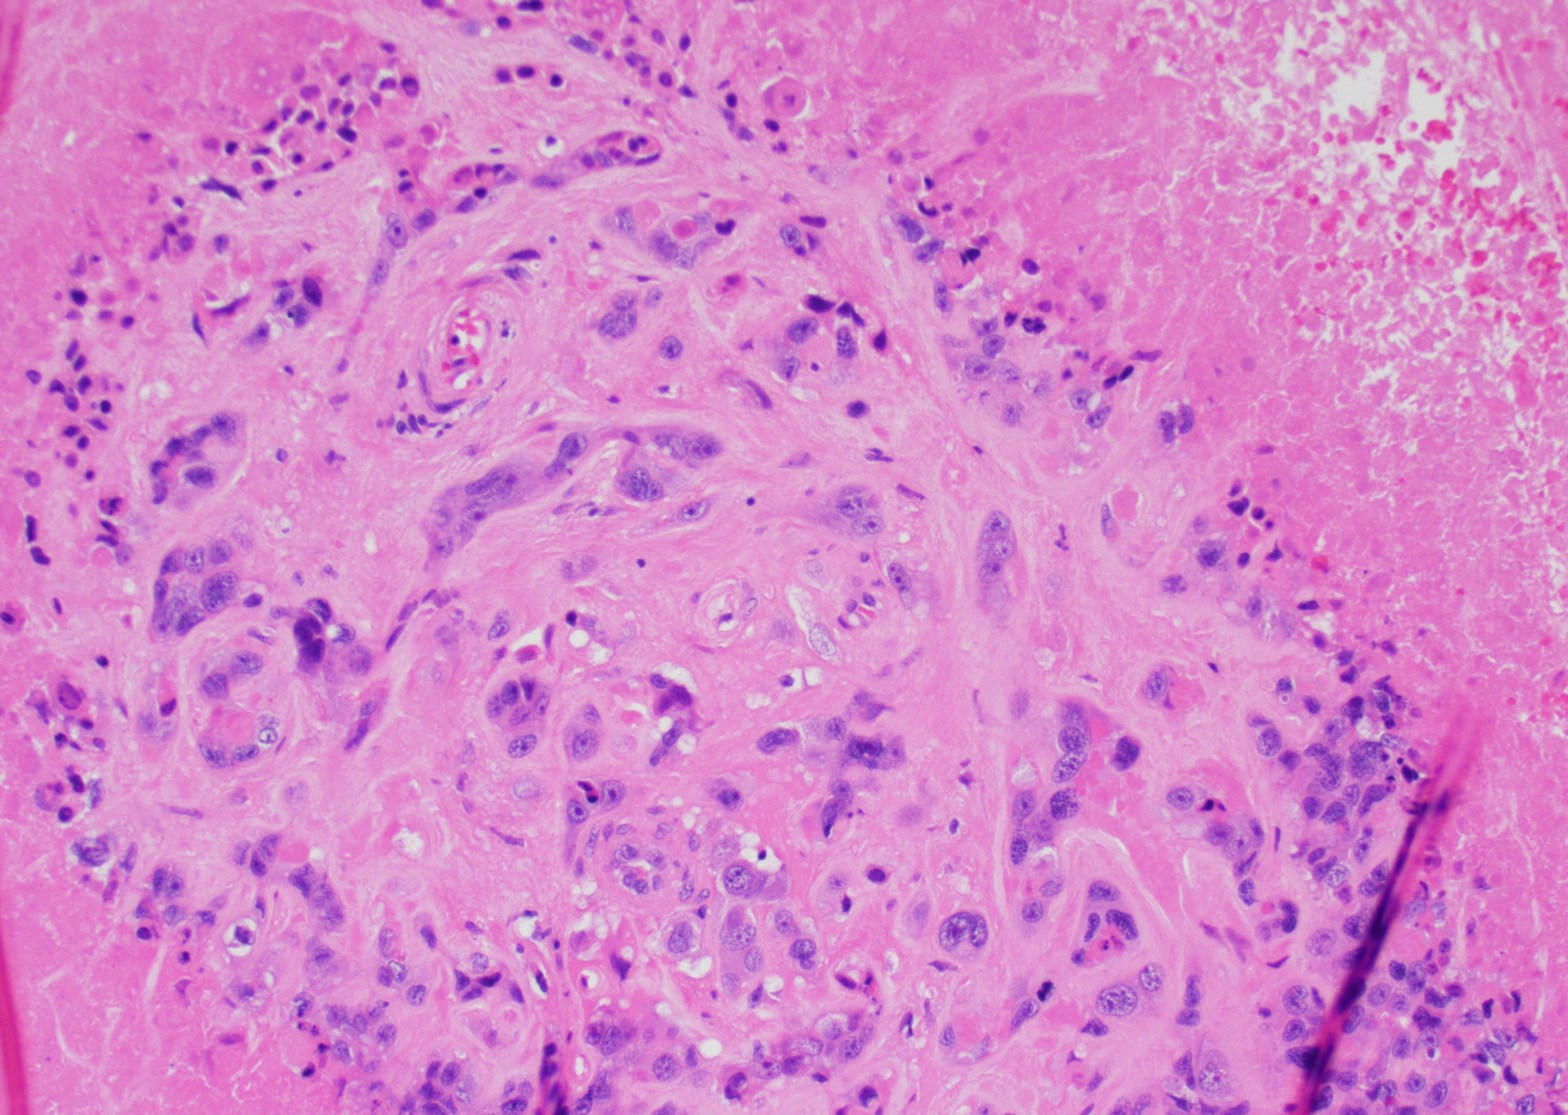

Microscopic examination: the lesion revealed nodular, expansile growth. The nodules were composed of epithelioid cells with abundant eosinophilic cytoplasm, frequent mitotic figures, and the background of necrosis. The nodules and the cells were embedded in the background of hyaline material (Figures 1-4). The cells were positive for GATA-3, alpha inhibin, cytokeratin, and negative for ER, PR, beta-hCG, p16, p53. The diagnosis of the epithelioid trophoblastic tumor (ETT) was rendered. Two years later she presented with new lung nodules. The biopsy showed a metastatic epithelioid trophoblastic tumor with the same immunophenotype. Immunohistochemistry for PD-L1 was positive.

Figure 1

Grossly, the tumor is a distinct lesion or a mass (required for the diagnosis). Microscopically, the cells grow in a nodular pattern with pushing invasion into adjacent structures. The neoplastic cells are large with abundant cytoplasm, arranged in nests and sheets. The mitotic rate is variable, and it ranges from <10 per 10 high-power fields to brisk mitotic activity. High mitotic count is a poor prognostic sign. The background of eosinophilic hyaline-like material is frequently present. Many times, like in our example, extensive geographic necrosis is noted.